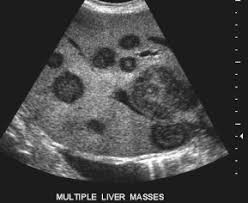

- cancer outside the liver